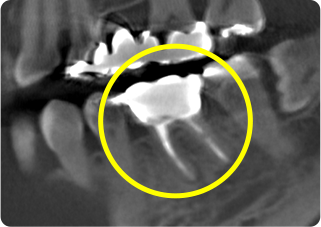

症例

術前

主訴 奥歯で噛むと痛い

治療期間/回数 1ヵ月、3回

価格(税込) 88,000円

リスク・副作用 病変再発、歯根破折の可能性

ポイント う蝕検知液を用い、むし歯の取り残しが無いようにし、ラバーダム防湿を行い、無菌的に根管治療を行った。根管充填材は、殺菌作用の強い保険適応外のMTAセメントを使用した。